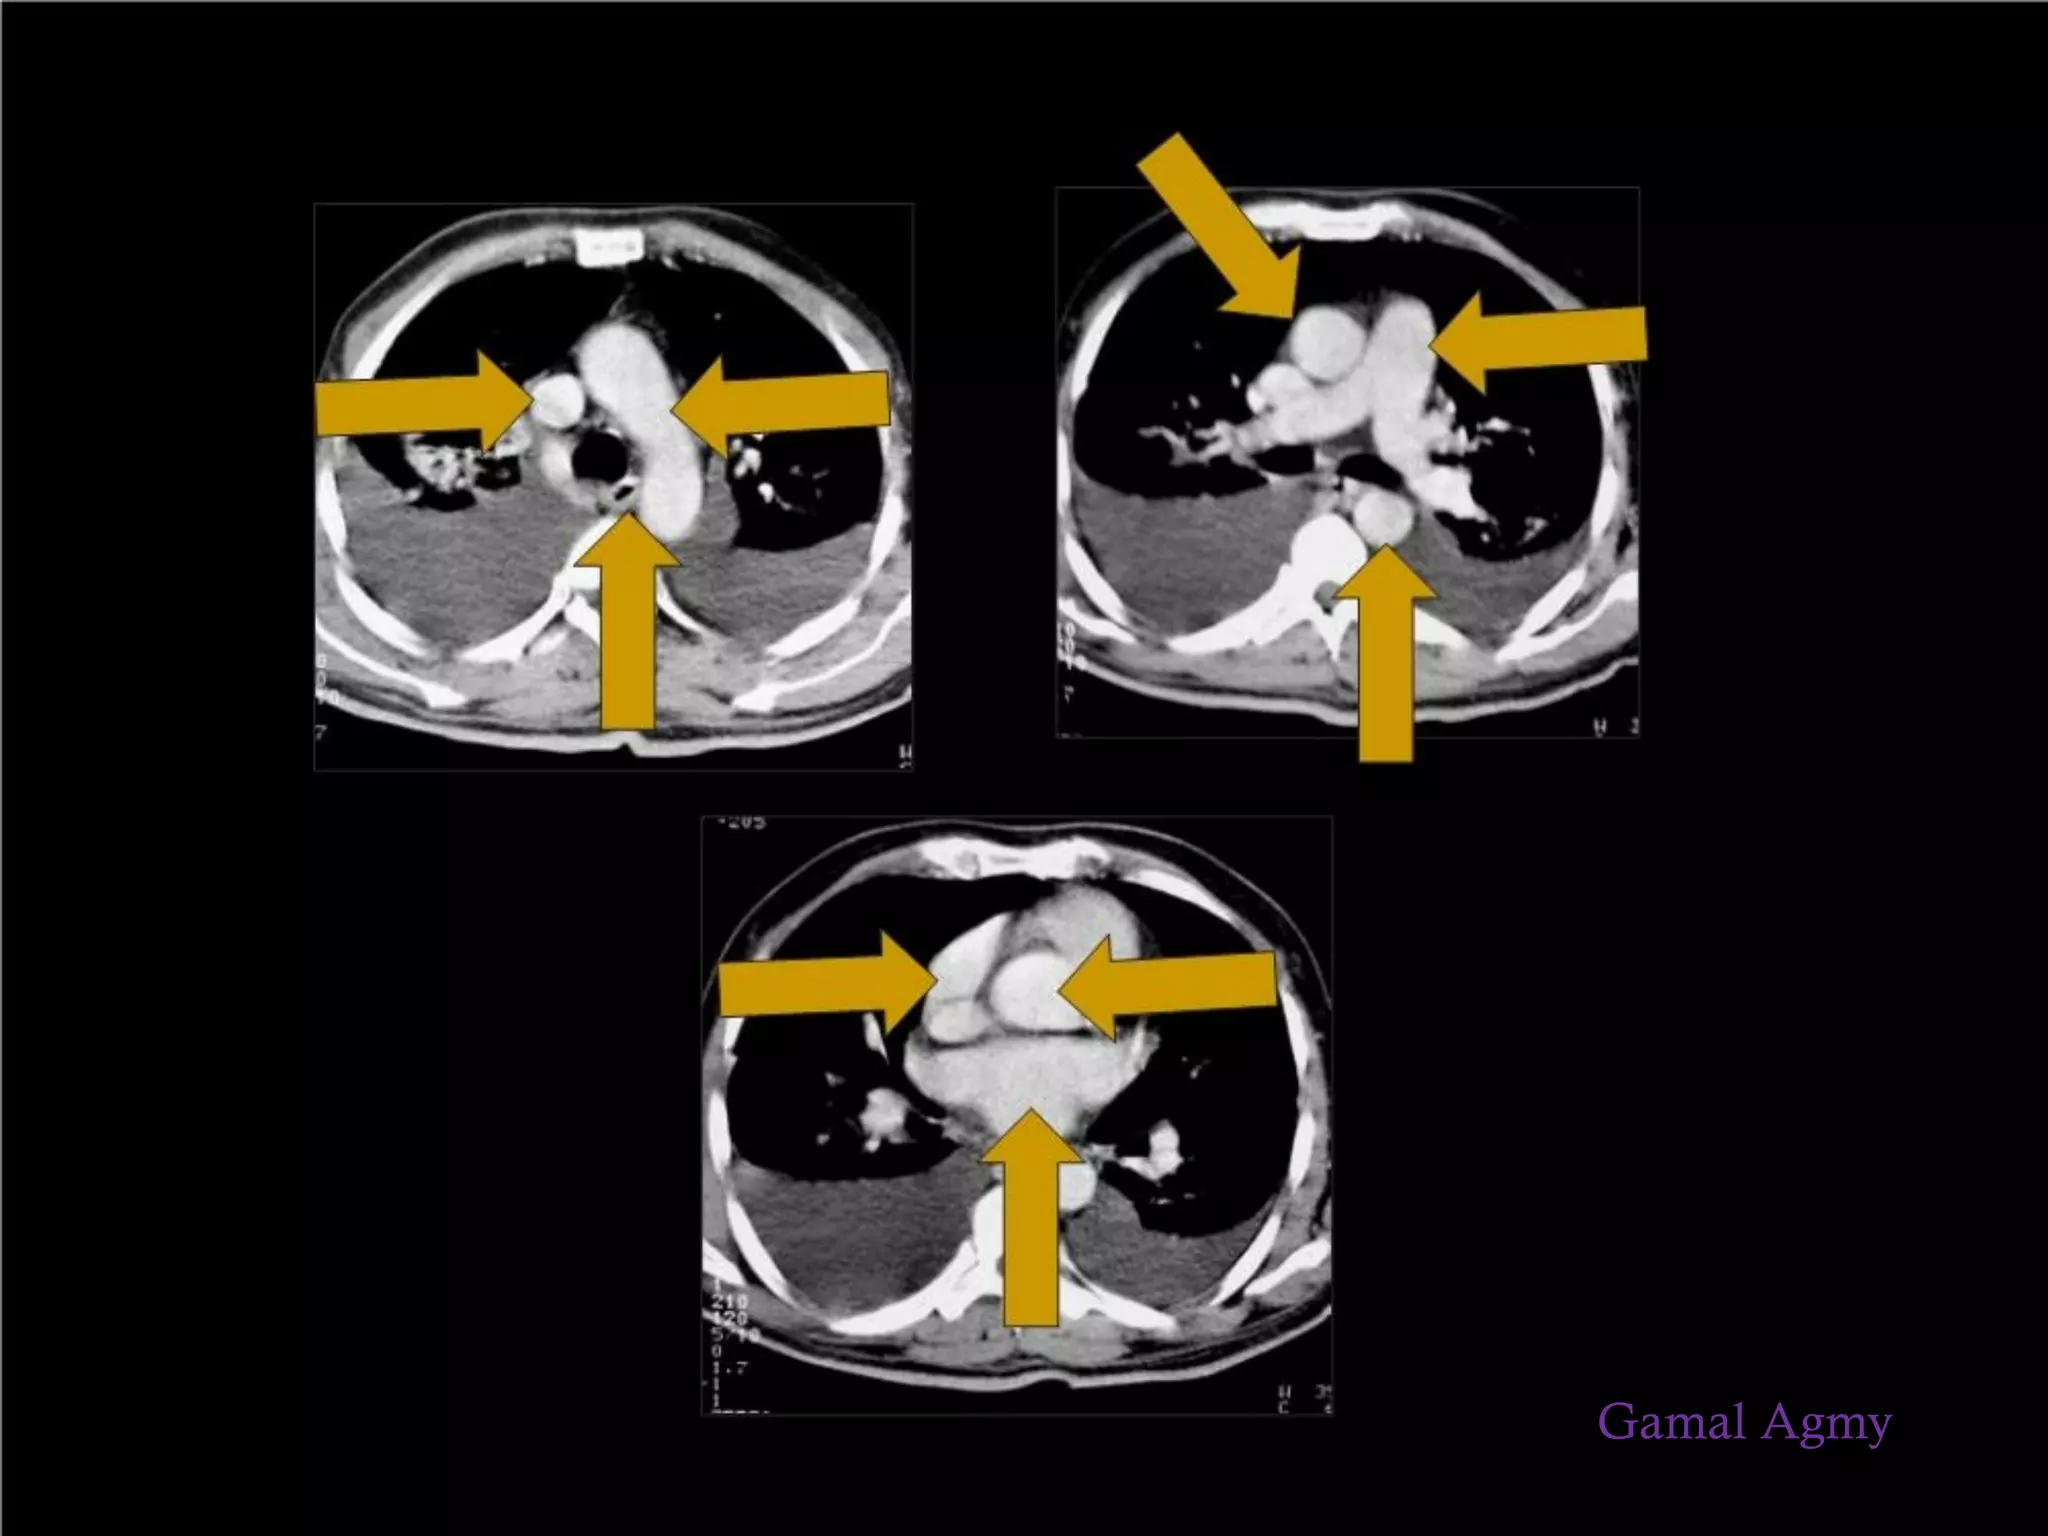

Mediastinal

origin?

 The main bulk of the lesion is present in the mediastinum

 Lesion arising from a mediastinal structure

 Obtuse angle of interface with the mediastinal border